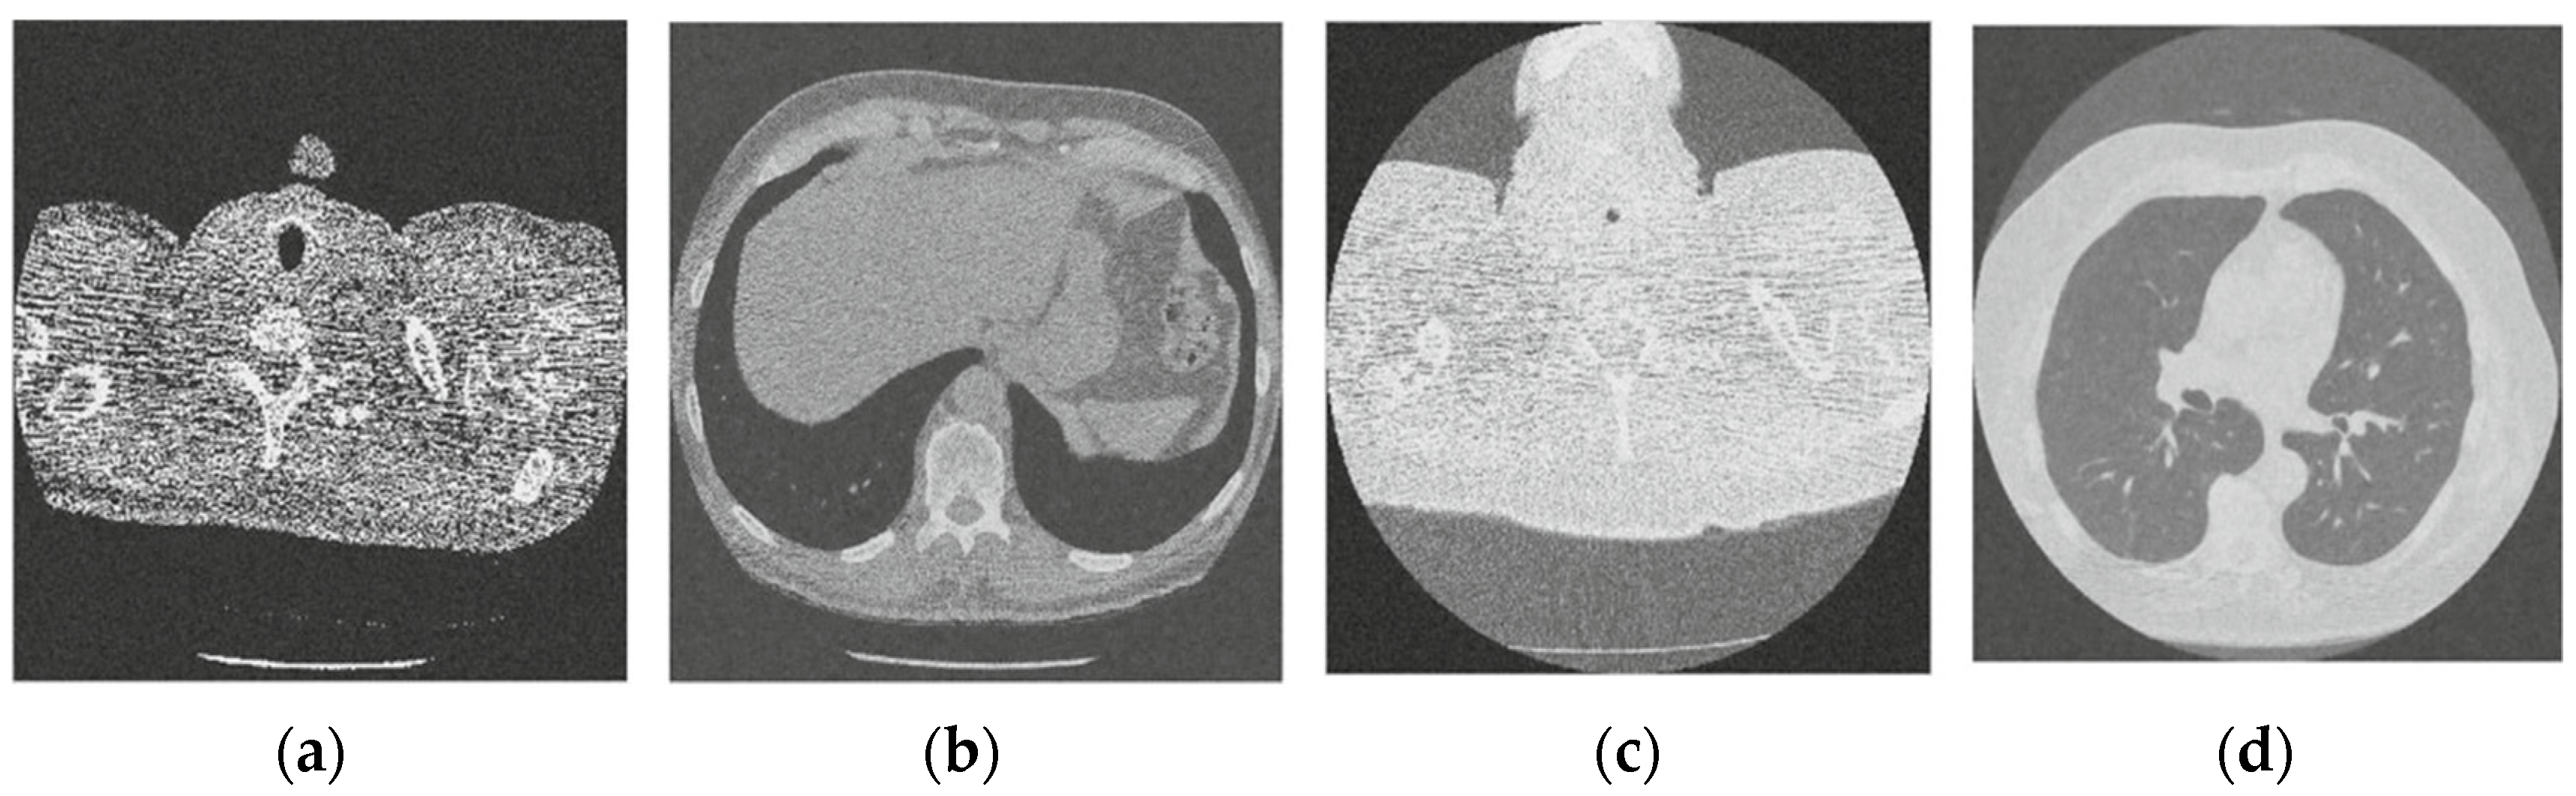

Figure 3 shows the corruption of a CT image after the addition of 20% Gaussian noise. The degradation in image quality is visible to the naked eye without aid when compared to the original CT image. Figure 4, Figure 5, Figure 6, Figure 7, Figure 8, Figure 9, Figure 10 and Figure 11 show the denoised CT images, corresponding to CT images in Figure 3 and generated from various denoising models. The results show a discernible reduction in both the gaussian noise introduced, as well as the noise present in the original CT image whilst safeguarding the finer details present in it.

Figure 7.

Result of image denoising method using CNN with batch renormalization [35]; (a) Denoised CT1 image; (b) Denoised CT2 image; (c) Denoised CT3 image; (d) Denoised CT4 image.

For effective comparison to other systems available out there, this system has been pitted against seven of the most robust and widely used denoising techniques out there, i.e., Figure 4, Figure 5, Figure 6, Figure 7, Figure 8, Figure 9, Figure 10 and Figure 11. All the denoising frameworks performed reasonably well, with similar levels of denoising in their outputs, within a certain margin of error and variations. The result from these techniques for four CT images is displayed in Figure 4, Figure 5, Figure 6, Figure 7, Figure 8, Figure 9, Figure 10 and Figure 11. The CT image manipulation gave rise to redundant overcorrection, cumulating in distortion of the black borders and the introduction of fuzziness. Only two CT images from the rivaling systems have managed to preserve the blackness of the outer borders in the CT images. The result from [45] in Figure 9c is the least clear, with distortion visible to the unaided observer. A similar problem is observed in Figure 4a,c, where the system overcorrects, introducing more distortion instead of improving clarity. Figure 10d comes closest to the original, though the proposed framework is superior, as illustrated in the next section. From Figure 11a–d, it is very clear that the proposed algorithm gives better outcomes in comparison to existing methods in terms of clinical features, such as edges, textures, contrasts, and brightness.